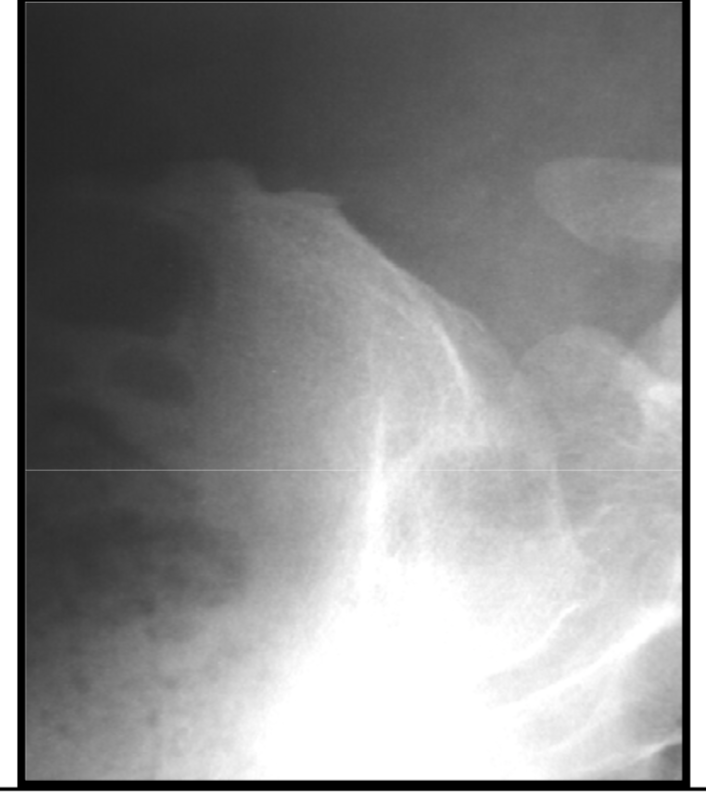

Paraglenoid sulcus – internal iliac artery

anat variation

Degenerative enthesopathy